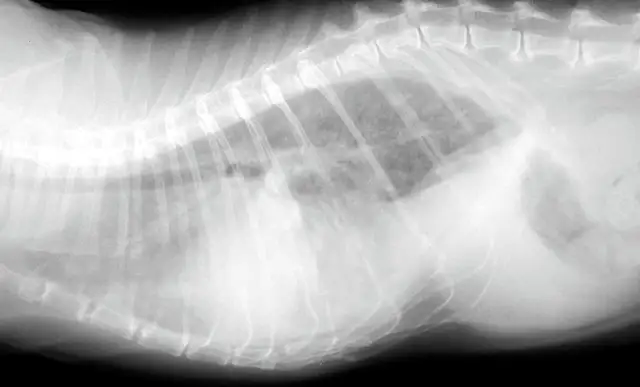

Once the patient is stabilized (often after 12 to 24 H), obtain radiographs (Figure 3) and echocardiography to confirm the diagnosis of CHF and to identify the nature and severity of the cardiac disease. The most common cause of CHF in cats is HCM; less common are dilated, restrictive, and unclassified cardiomyopathy. Murmurs associated with HCM are usually created by mitral regurgitation, abnormal displacement of the mitral valve during systole (systolic anterior motion or SAM), causing left ventricular outflow tract obstruction, or dynamic right ventricular obstruction either in combination (e.g., mitral regurgitation is always present with SAM) or alone (mitral regurgitation can also occur without SAM) (Figure 4).

FIGURE 3 Lateral (A) and dorsoventral (B) radiograph of a cat with pleural effusion and suspected cardiomegaly; the radiograph was obtained after stabilization.